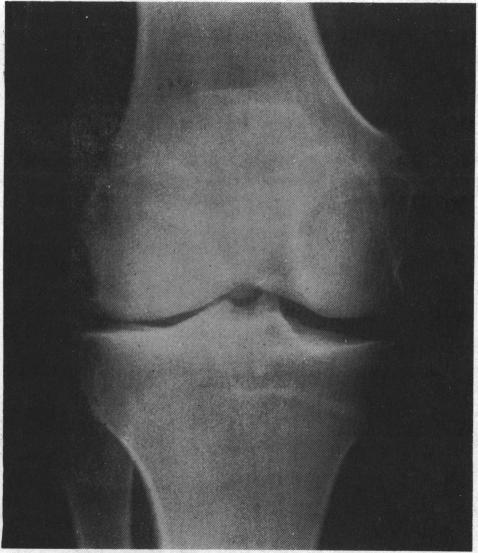

Associated factors in recurrent groin and hamstring injuries.

Br J Sports Med. 1982 Mar;16(1):37-9. doi: 10.1136/bjsm.16.1.37.